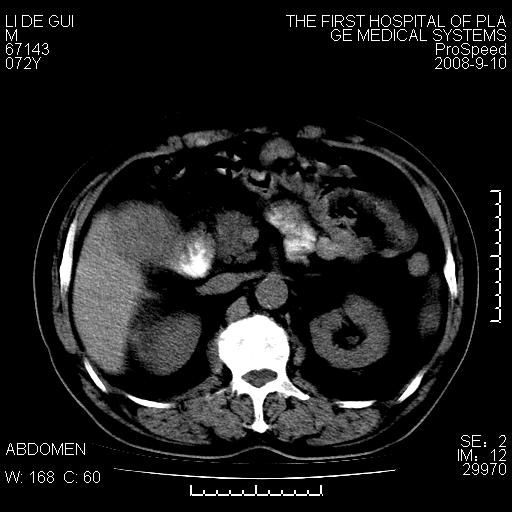

标题: CT17988:腹部肿块两年,肿块大小无变化,患者无不适,自我 [打印本页]

标题: CT17988:腹部肿块两年,肿块大小无变化,患者无不适,自我

胆囊占位性病变(黄色肉芽肿性胆囊炎?)。

考虑-----胆囊血肿机化或胆囊癌或腺肌增生症------增强

胆囊占位性病变,增强。

十二指肠的间质瘤